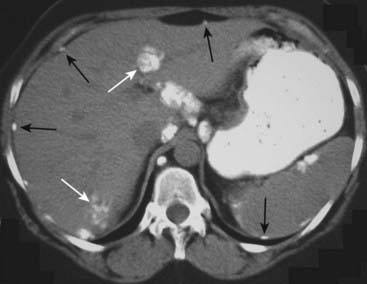

Figure 16-14 Calcified ovarian metastases.

An unenhanced axial CT scan of the upper abdomen shows multiple amorphous calcifications, some within the liver (solid white arrows) and others that stud the peritoneal surface of the abdomen (solid black arrows). This patient had a mucin-producing adenocarcinoma of the ovary that metastasized to the peritoneum and liver. Mucin-producing tumors of the stomach and colon can also produce calcified metastases, but ovarian malignancy would be the most common to metastasize to the peritoneum.